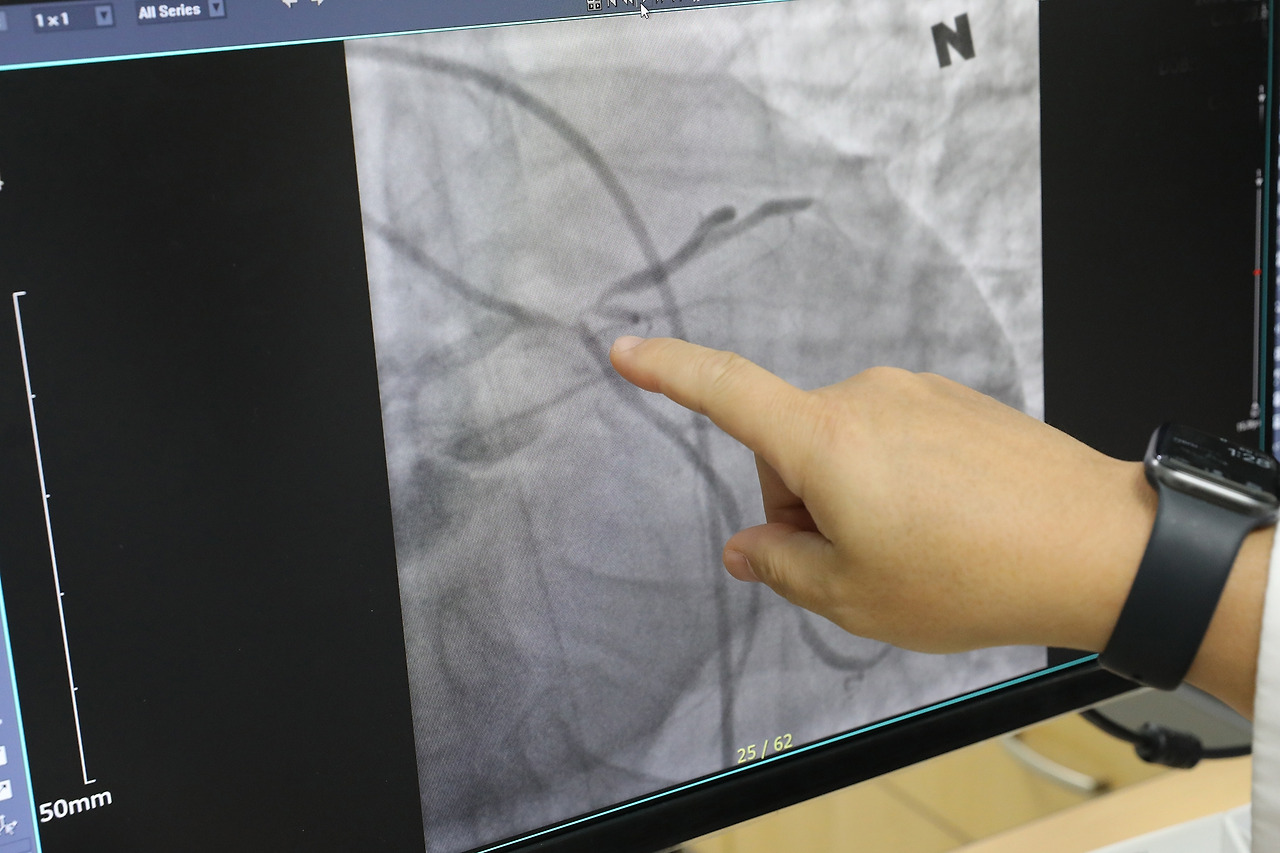

[사진] 심장혈관(관상동맥)이 막혀있는 심장마비 환자 검사 영상.jpg [사진] 심장혈관(관상동맥)이 막혀있는 심장마비 환자 검사 영상